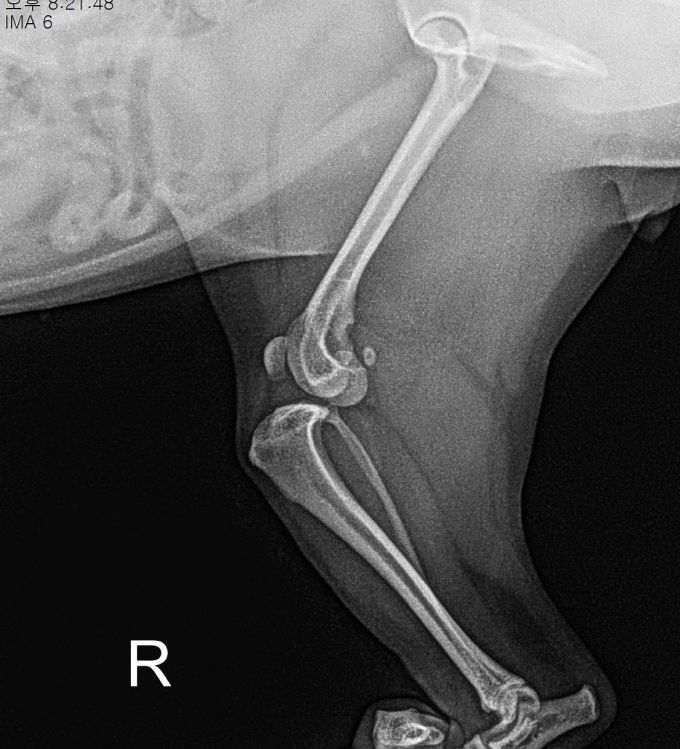

BEFORE